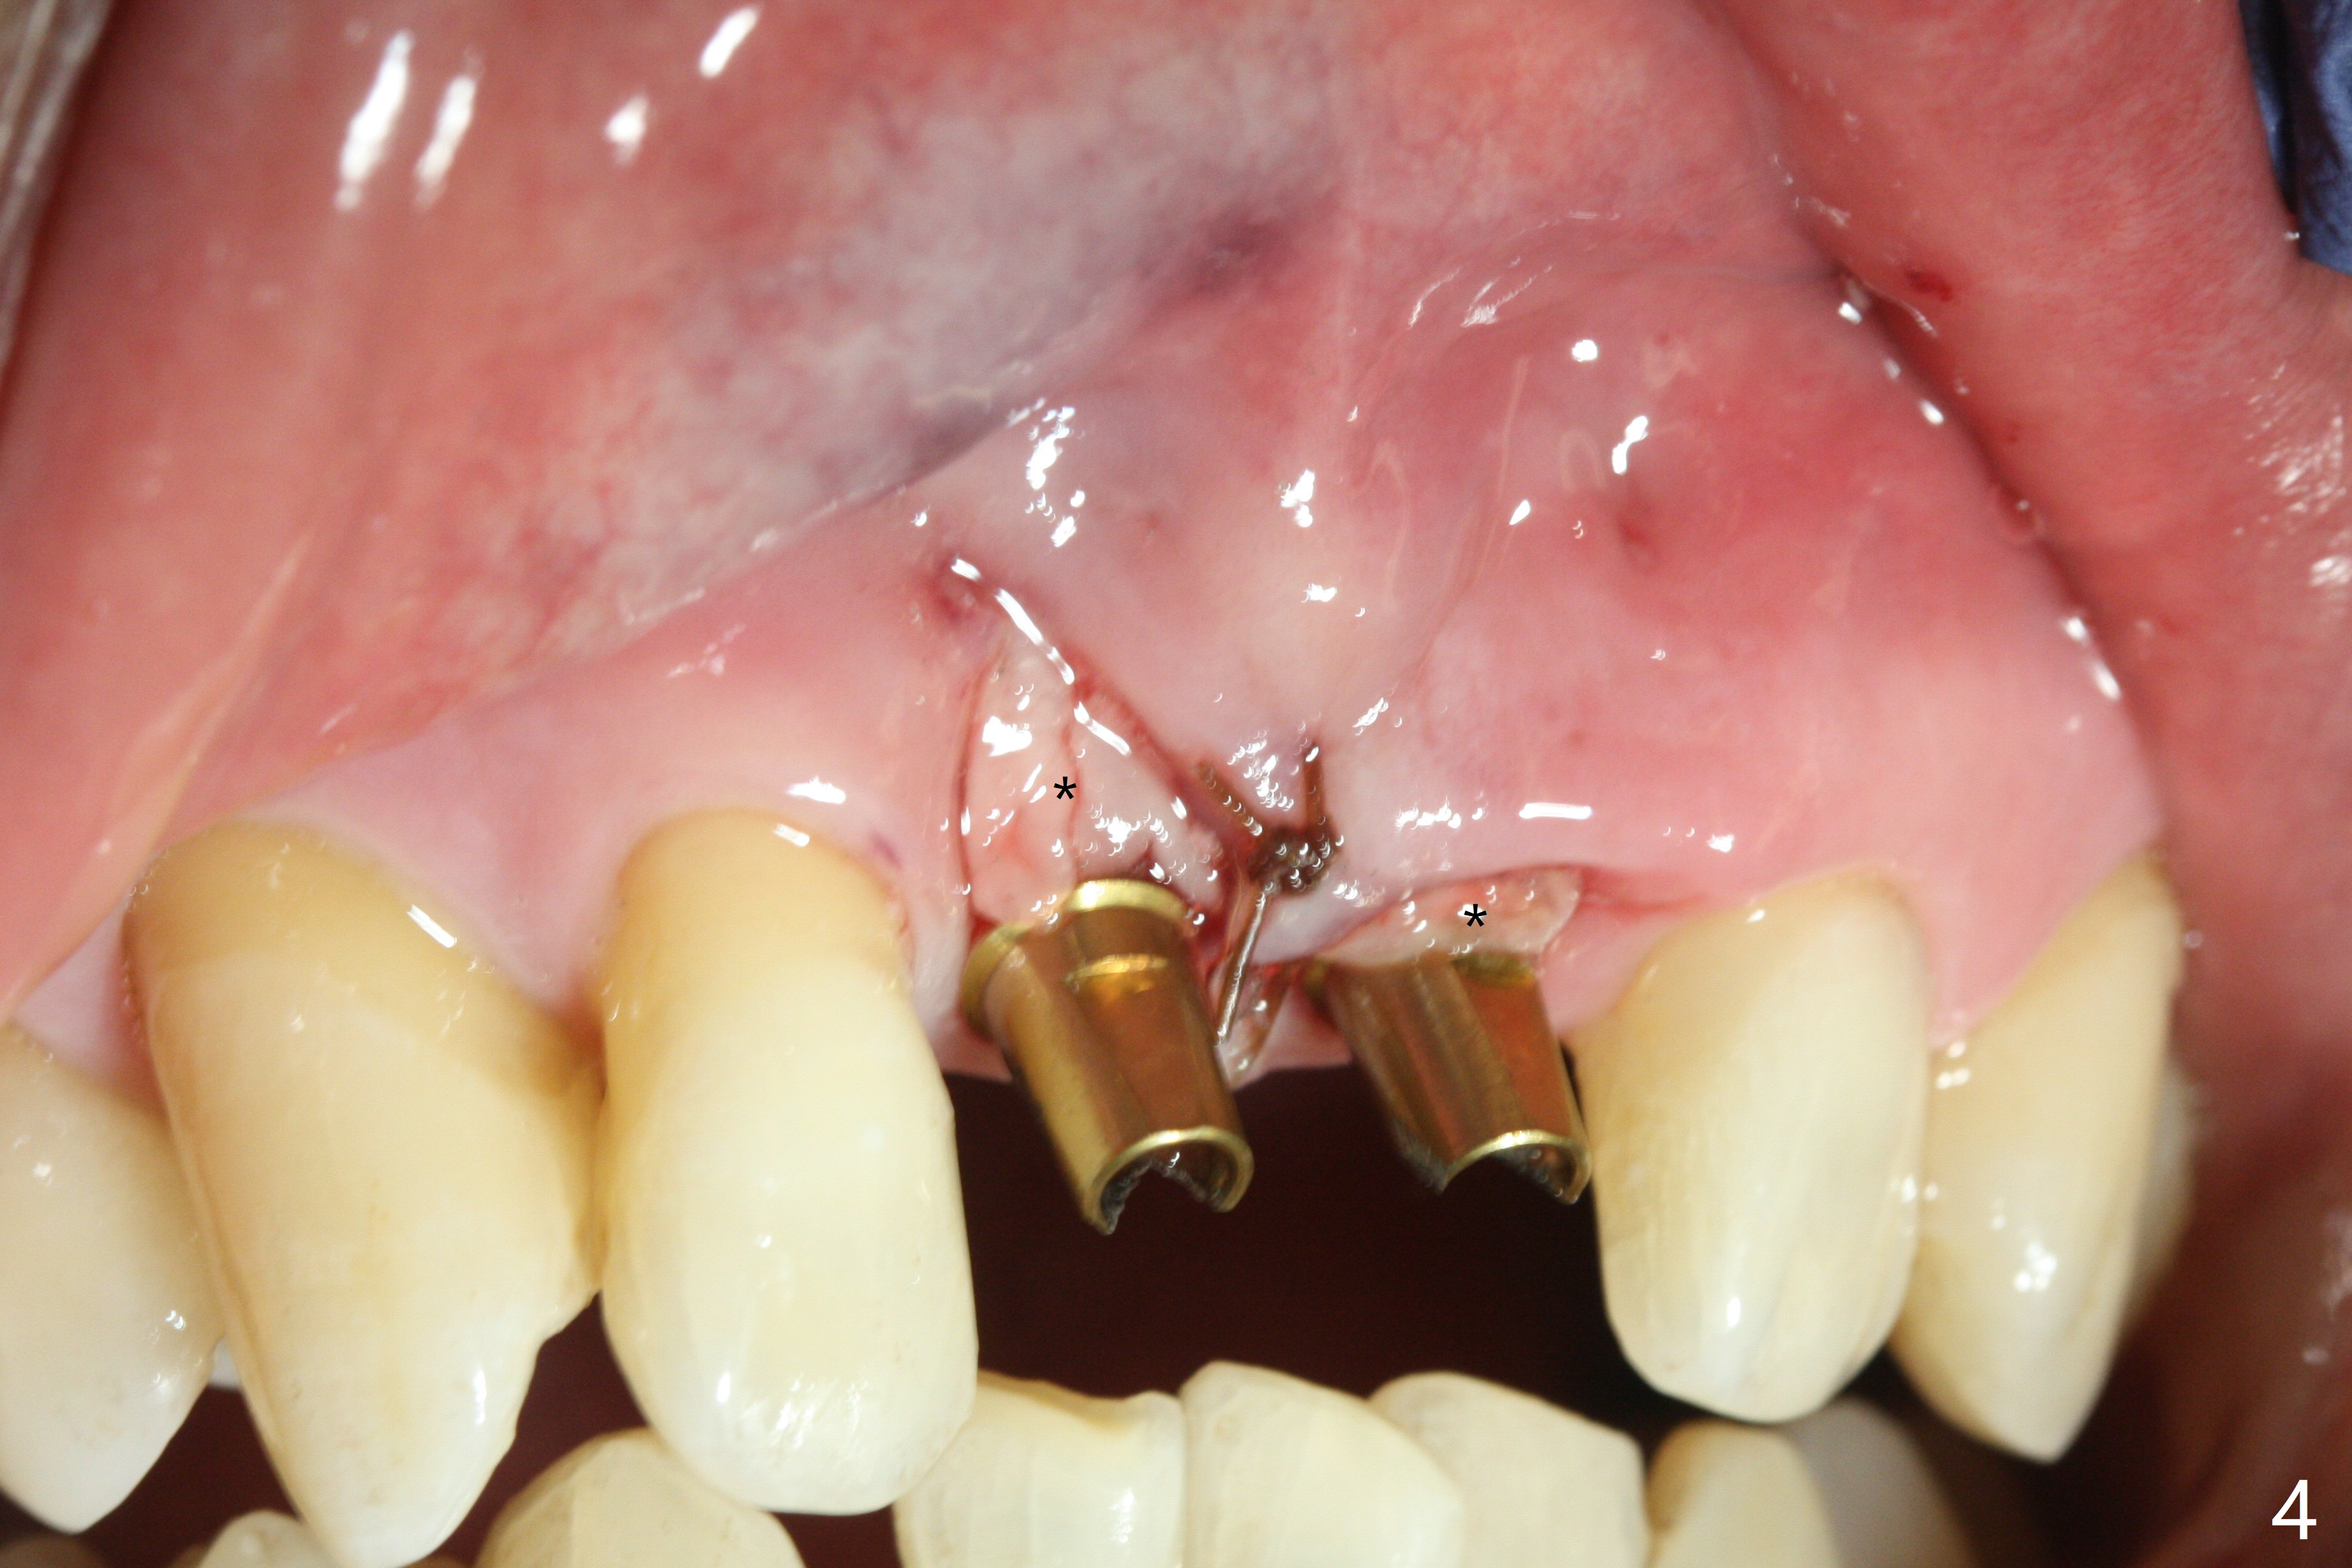

There is no buccal plate at #8 or 9 when the teeth are extracted as well as severe soft tissue defect at #8. Osteotomy is initiated as palatal as possible (Fig.1). When 3.5x13 mm implants are placed initially, the one at #8 is supracrestal (Fig.2 ^). To reduce the chance of peri-implantitis, the implant is placed deeper (Fig.3 (~2 mm implant threads exposed buccally)) with placement of sticky bone around the implants and 4.5x5.5(4) mm abutments (Fig.3 *). The buccal soft tissue defect #8 is repaired with a piece of PRF membrane (Fig.4 *), followed by periodontal dressing. Smaller 2-piece implants (3 mm, IBS) with smaller abutments (4 mm) may further reduce chance of periimplantitis and easy buccopalatal reduction of the abutments for restoration. The periodontal dressing remains stable 7 days postop (Fig.5) because it wraps around the abutments (Fig.6 A). By the time the periodontal dressing gets loose, #8 buccal soft tissue defect should be healing. When breaking-down periodontal dressing is removed 17 days postop, the coronal abutments and bone graft are exposed; after fabrication of provisional crowns (Fig.7), periodontal dressing is re-applied buccally. When the second dressing dislodges 5 weeks postop, the buccal soft tissue appears to reduce (Fig.8). Raising flaps may be less traumatic. A piece of bone graft is being extruded 4 months postop (Fig.9 >). After the abutments change from 4.5x5.5(4) to 4.5x7(3) mm, new temporary crowns are fabricated (Fig.10 (4.5 months postop)). CT shows apparent buccal bone at #8 and 9 (Fig.11,12). How to improve cosmetic?